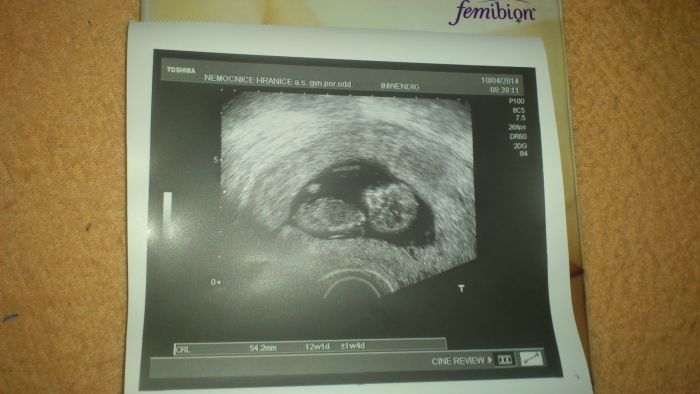

Holky, tak píšu jen dobré zprávičky z kontroly.. Jsm úplně nadšená, jak jsem miminko zase viděla.

Úplně sebou házelo a nechtělo se změřit, ale nakonec se umoudřilo a máme 54 mm, a jsem už 11+6 . Měla jsem být 11+4, tak jsem o dva dny poskočila dopředu.. Já jsem tak spokojená :-)

Taky mi měřili tlak, vzali si moč a požádala jsem o odběru krve na toxoplazmózu (mám kočku). V popndělí screening, tam prý na 70% poznají pohlaví.. Tak se moc těším.. Říkal, že všechno vypadá moc dobře..

Jo a stanovil mi termín porodu 24.10.2014 :-)

jinak krasna fotecka

Je Tynuskooo krasny moooc. Zavidim Ti. Uz chci taky screening. Mam z Tebe radost. Jak si tam pekne haja.